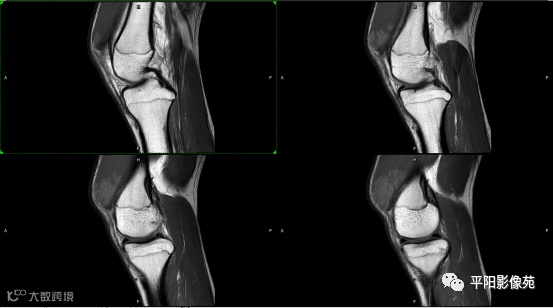

影像表现:

左膝关节股内侧肌内见多房样短T1长T2信号,内可见分隔,增强扫描明显强化,分隔未见明显强化,病灶局部与股骨远端分界不清。